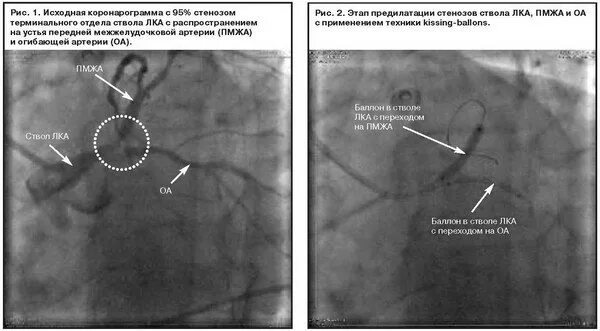

Стеноз проксимального отдела